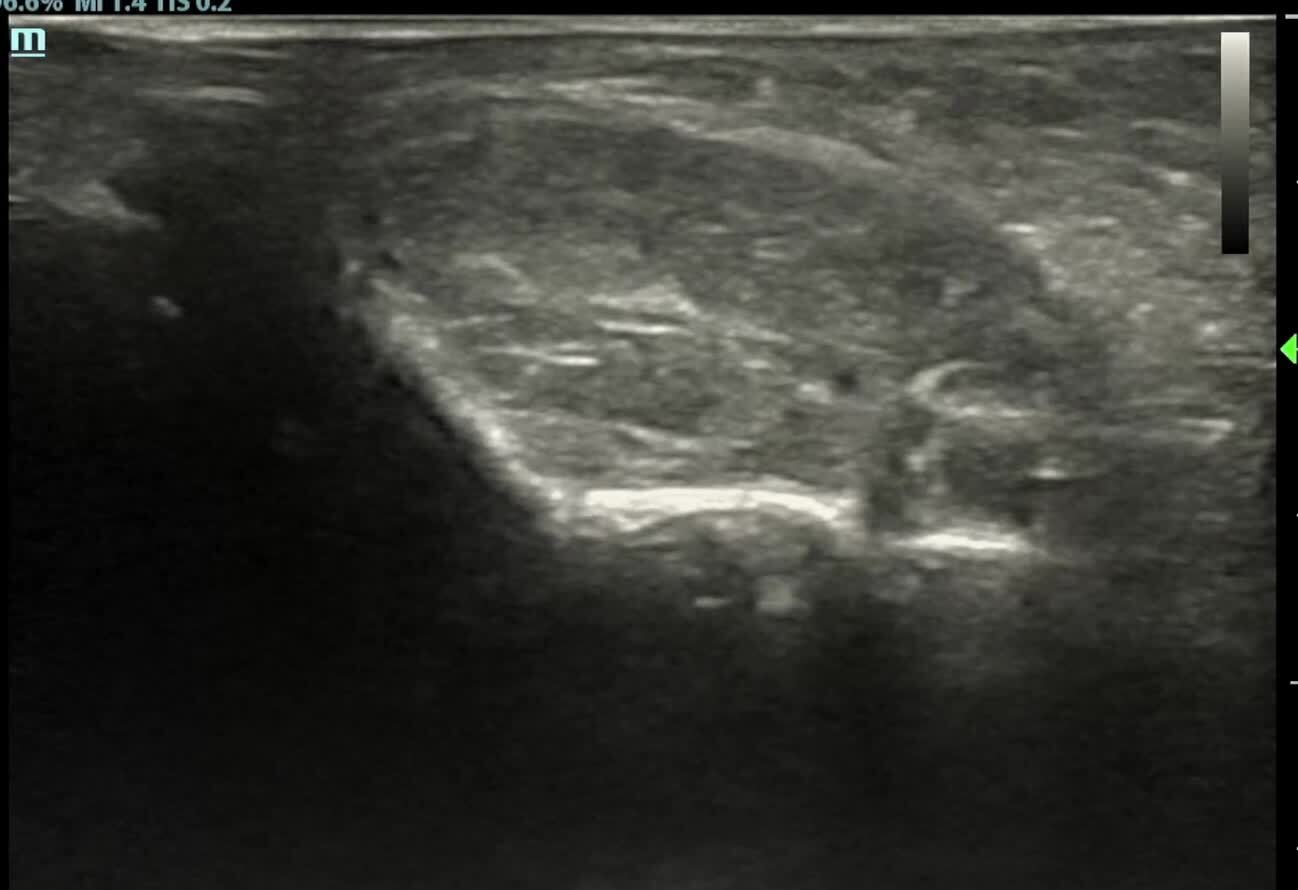

淋巴管瘤患兒家長長長被多次注射治療的痛苦經(jīng)歷所折磨,如何提高單次注射有效率成為每位實(shí)施注射治療醫(yī)生追求的目標(biāo),本人經(jīng)過在浙江省腫瘤醫(yī)院超聲科培訓(xùn)后實(shí)施了超聲引導(dǎo)下淋巴管瘤逐個囊腔注射治療的方法,效果顯著,現(xiàn)向大家介紹:1.先看下面的超聲影像,這是一個相當(dāng)復(fù)雜色淋巴管瘤,外院盲穿刺下注射治療,已經(jīng)將大的容易的治療了,小的多囊的殘留,治療難度系數(shù)至少四顆星。2.看看我們是實(shí)際治療經(jīng)過吧。最后各個囊腔在穿刺針的穿刺給藥后可見全部相同,白色的藥物全部注射在瘤腔內(nèi)保證單次注射治療的最大效果。3.來看個簡單一點(diǎn)的吧,其實(shí)也不簡單,頸部的多囊腔淋巴管瘤,視頻有點(diǎn)長,無剪輯無偽裝的超聲實(shí)時錄像。本人保證以最大的努力治療每一個就診的患兒,不會辜負(fù)您的信任。